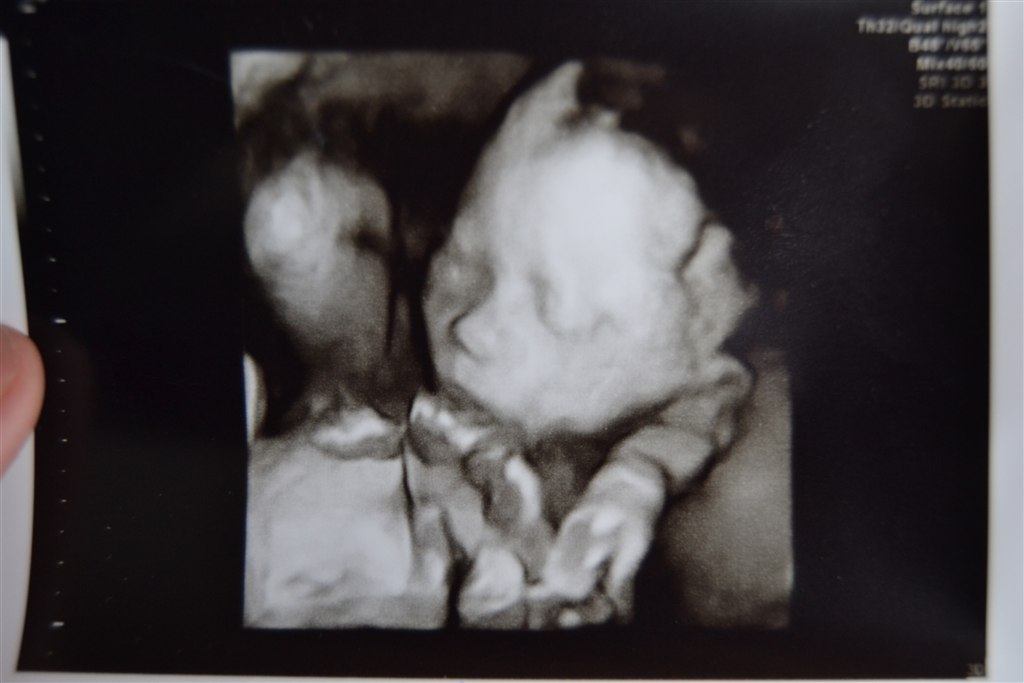

Der er et helt nyt mave billed og et 3D billed af trilling C....